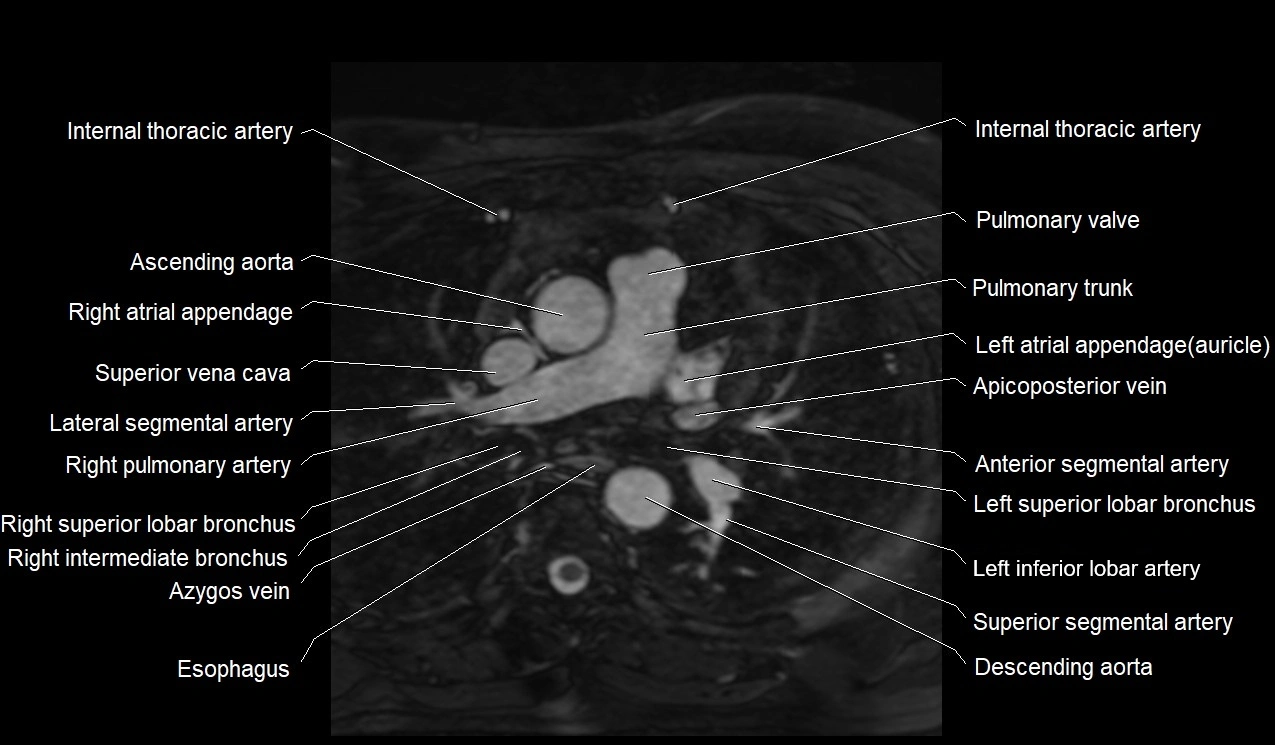

MRI image